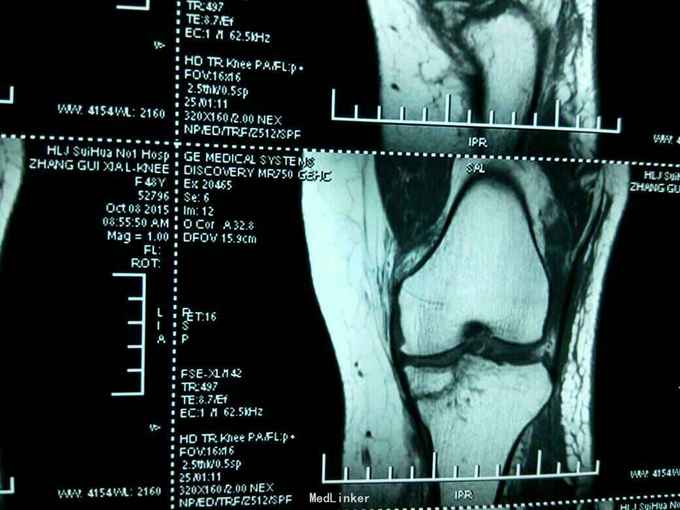

患者女性,48岁。因摔伤左膝关节,肿胀,畸形,活动受限二小时来诊。病人于二小时前滑倒摔伤,当即左膝关节肿胀畸形,局部肿胀,不敢下地行走。门诊拍片示:左膝关节胫骨平台塌陷骨折。以:左胫骨平台塌陷骨折收入院。

左膝关节局部肿胀,局部压痛。浮髌试验阳性。膝关节屈伸活动受限。不能下地行走。侧方应力实验阴性。抽屉实验阴性。拍片示:左胫骨平台骨折。核磁共振示:左胫骨平台塌陷骨折。局部骨质塌陷约1cm

左膝关节胫骨平台塌陷骨折。入院后,急诊在硬膜外麻醉下行切开复位内固定术。于胫骨内侧切口。局部开窗,撬拨恢复关节面平整。取同侧髂骨骨块置于开窗处。植骨确实。局部锁定钢板内固定。